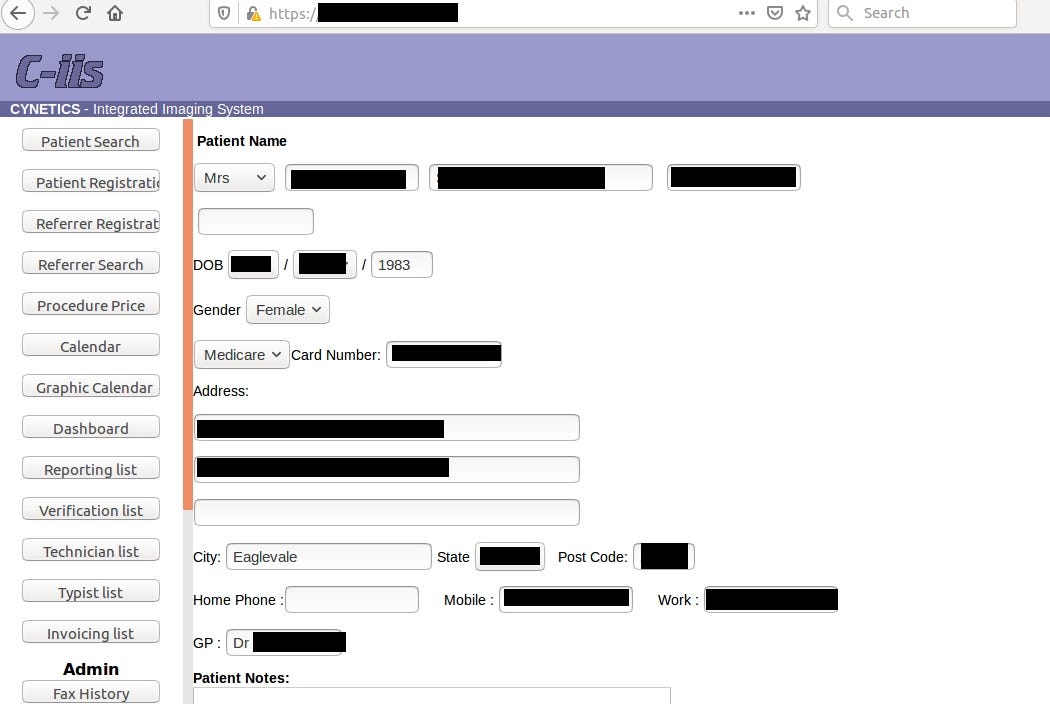

In this case leak contained 4,5 TB of data including radiology photos of pregnancies with diagnosis (almost 2M images!), invoices or personal patient’s data.

Going back to the main topic and the most important data in the leak, each patient has from 10 up to 40 radiology photos with description.

Frankly speaking, it says nothing for me but for someone acquainted with the topic it’s trove of information about health of patient and her fetus.

If someone is reading this article and used their service, she should be aware that her medical and personal data might have been compromised.